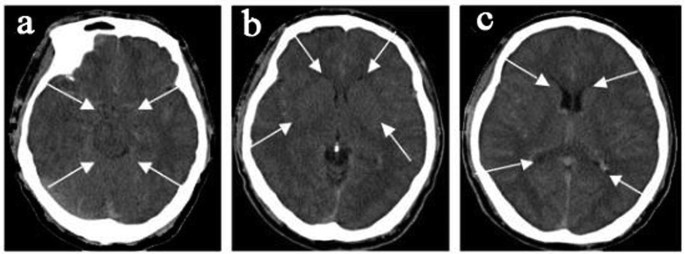

All 45 subjects had brain imaging; of the nine hospitalized patients with encephalopathy eight had CT and one had MRI. CT imaging in the hospitalized group showed diffuse cerebral edema with small ventricles and effaced sulci, as exemplified in Fig. 1. Two of these patients in addition to edema had multiple old cerebral infarcts, and one had chronic thrombosis of the superior sagittal sinus. The brain blood density (CT value of Hounsfield Units, HU) of the bilateral middle cerebral arteries and the superior sagittal sinus was greater in CMS compared to non-CMS groups (Table 1 and Fig. 2). The MRI was obtained in a patient who did not have CT. This 51-year-old female Han Chinese with CMS had resided at 3800 m for 15 years, suffering from headache, dizziness, fatigue, poor appetite, sleepiness, mood changes, and loss of memory for many years. Ten days prior to admission, she developed severe headache, vomiting, irritability, lethargy, and ataxia. Hemoglobin was 24.1 g/dl on admission and 15.4 g/dl after two-month’s treatment that included staying at the lower altitude, as well as oxygen, dexamethasone, and furosemide acutely, followed by Tibetan herbs. CSF pressure was 22.5 mmHg on admission. Initial MRI (Fig. 3) showed markedly increased T2 signal in cerebellar hemispheres, internal capsule, and parietal and occipital lobes that resolved after recovery two months later (Fig. 3). With recovery, apparent diffusion coefficient (ADC) values decreased in the cerebellar hemispheres from 1.26 ± 0.1 to 0.70 ± 0.06 (10−3 mm2/s) (Fig. 3a left& right), and from 0.97 ± 0.07 to 0.75 ± 0.02(10−3mm2/s) (Fig. 3b left & right) in other regions.

CT shows diffuse cerebral edema with small ventricles (c), effaced sulci (b,c), and compromised cisterns (a,b).